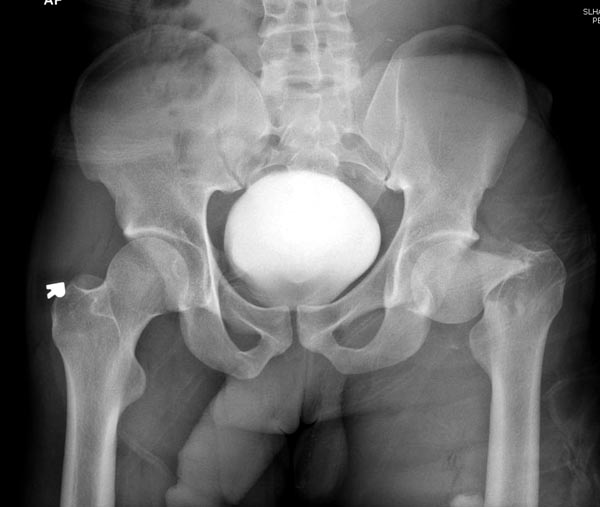

Пока надо делать снимки в классических укладках, т.е. хотя бы в двух

проекциях. А по тактике из всех переломов: шейка является приоритетным и

ургентным. Идеально фиксировать канюлированными винтами, но усложняется

тем, что имеется перелом верхушки вертела. Навряд ли получится закрыто,

надо открывать. Все зависит от возможностей на месте (писали насчет

DHS), можно и интрамедуллярный гвоздь, но не надо укорачивать, только

пустить overlapping, т.е. пластина от DHS покрывает часть гвоздя.

Здесь выставлен ренгенограммы больного, ему 21, травму получил в

результате высокоскоростной погони на украденной машине, которая

закончилась смертью трех остальных“боевых комрадов”. Начатую коллегой

открытую операцию на шейке пришлось закончить мне, установкой винтов и

ретроградной фиксацией бедра. Выписка в обычное сроки и наблюдался

амбулаторно. Каждый раз напоминали о возможности осложнений ввиде

несращения! По истечению 4 месяцев появились признаки варусной

деформации. На СТ срезах несращение шейки и бедра. Риминг, замена на

более толстый гвоздь и вальгусная остеотомия.